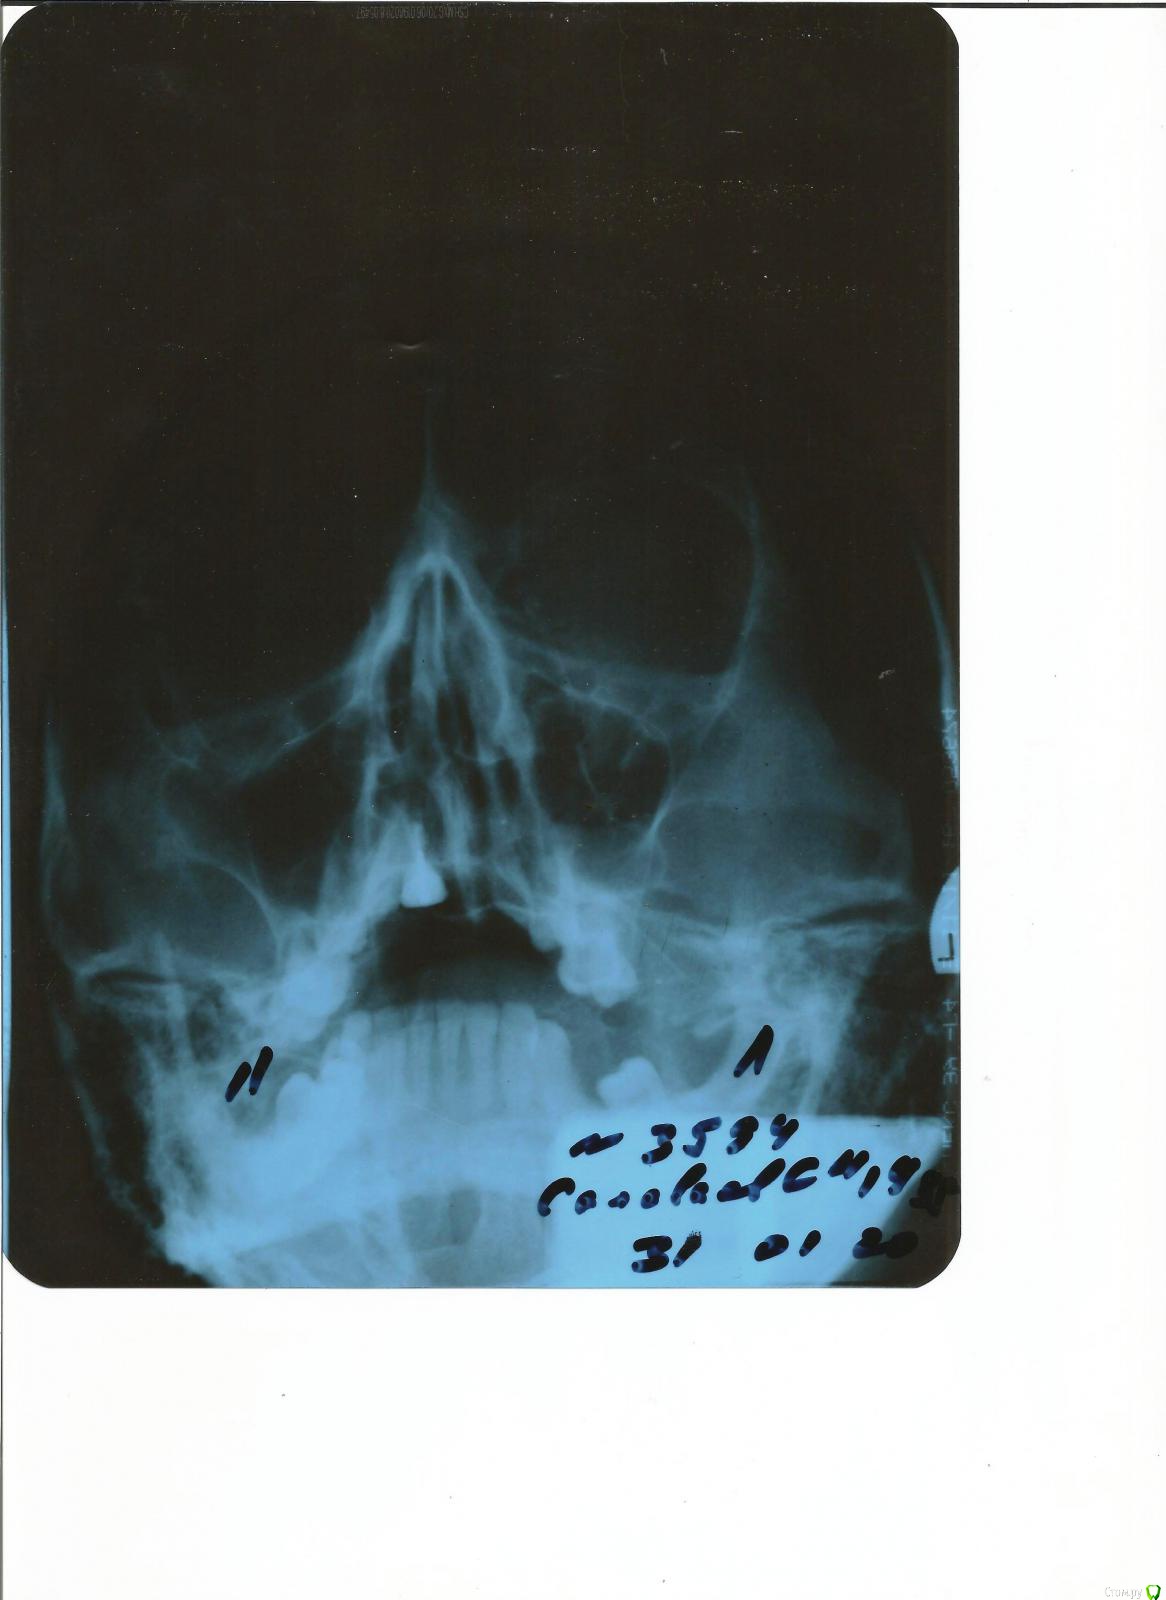

streptocid Опубликовано 28 марта, 2020 Поделиться Опубликовано 28 марта, 2020 (изменено) Добрый день, примерно пол-года я назад удалил вверху зуб, стало болеть вернее небо, десна там немного вздулась, вот снимок посмотрите пожалуйста Изменено 28 марта, 2020 пользователем streptocid Ссылка на комментарий

It'sGeorgy Опубликовано 28 марта, 2020 Поделиться Опубликовано 28 марта, 2020 Снимок, к сожалению, неинформативный совсем. Попробуйте сфотографировать то место, которое вас беспокоит. 1 Ссылка на комментарий

streptocid Опубликовано 31 марта, 2020 Автор Поделиться Опубликовано 31 марта, 2020 Я конечно не хочу никого обидеть и оскорбить, но есть тут люди которые реально разбираются в рентген снимках и которые могут реально написать что по снимку? Весь верх покраснел у меня, фото сейчас не могу скинуть, до ЧЛХ до вторника тоже не могу доехать COVID-19 у меня в городе ничего не работает сейчас, даже подстричься и кофту себе купить сегодня не смог.. Можно просто сделать доброе для человека распечатать этот снимок и показать профессору из института? Добро ведь вернется добром потом Ссылка на комментарий

red_butler Опубликовано 31 марта, 2020 Поделиться Опубликовано 31 марта, 2020 Скорую вызывайте. Фото Ваше не информативно Ссылка на комментарий